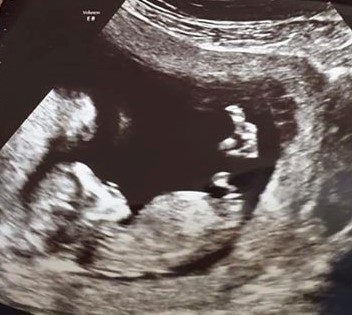

Hi, Are these images showing nubs, I can't be sure of what I'm looking at which line is the nub? Can anyone give a guess of gender? Thanks so much in advance.

It's a bit early for my liking, I'll give a tentative pink lean but that nub can still rise at this stage.

The nub is that "y" shape coming from baby's bottom.

It's the same thing, just doesn't capture the Y shape. It's still pointing downward, though. It can still rise and be a boy, but I guess girl.